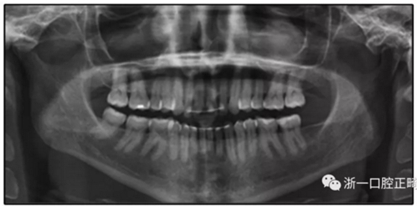

患者是一名39歲的白人婦女,病史不明。她主訴是她的右側(cè)顳下關(guān)節(jié)有不適癥狀,并希望改善她的笑容。她有一個對稱的臉型和一個II類2分類的微笑。她的側(cè)貌是凸的,90°的鼻唇角和骨性下頜骨發(fā)育不足??趦?nèi),上頜中線與面部重合,但下頜中線向右側(cè)偏移5mm;存在6mm的深覆蓋。她的兩側(cè)都是I類磨牙關(guān)系,左側(cè)是I類尖牙關(guān)系,右側(cè)是完全的II類尖牙關(guān)系。下頜右側(cè)第二前磨牙先天性缺失(圖1和圖2)。最初的全景片顯示了足夠的骨質(zhì)水平和全部的第三磨牙(圖3)。治療前的頭影測量片片和相應(yīng)的頭影測量圖(圖3)證實ANB為7°,Wits評估為6 mm的骨性II類錯合(表)。上頜切牙相對與面部和顱底的位置很好。下頜切牙前傾。診斷為II類2分類錯合畸形,伴有骨性下頜發(fā)育不足,右側(cè)顳下頜關(guān)節(jié)癥狀,下頜中線向右側(cè)偏移5mm,先天性右下第二前磨牙缺失。

圖3. 治療前頭影側(cè)位片,頭影測量描跡圖和全口X光片